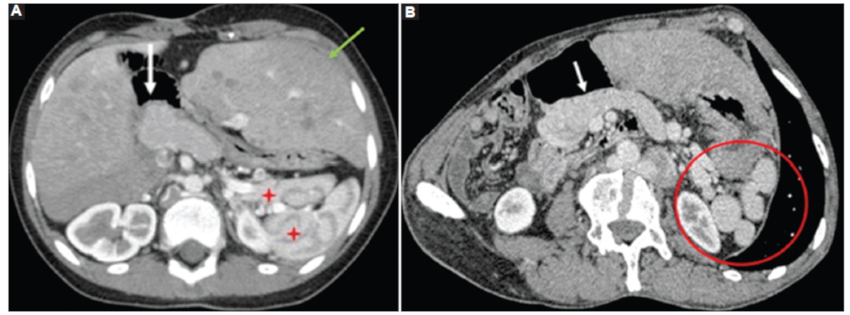

Corazón

En el caso 2 se observó dextrocardia con ambas aurículas de morfología izquierda y comunicación interauricular tipo seno venoso adyacente a la inserción de la vena cava superior. En un tiempo precoz luego de la administración de medio de contraste se demostró opacificación de la aurícula contralateral, lo que sugiere shunt derecha-izquierda (Fig. 2 A y B). En el caso 3 se evidenció corazón unicameral con canal auriculoventricular (Fig. 2C).

Hígado

En el síndrome de heterotaxia, la disposición central del hígado «en puente» es habitual junto con la vesícula biliar cercana a la línea media (casos 1, 2 y 3) (Fig. 12). En los casos 1 y 3 se observó remodelación hepática con hipertrofia del lóbulo izquierdo y del lóbulo caudado, determinando en el caso 3 una gran hepatomegalia (Fig. 12). Los casos 2 y 3 presentaron la vesícula biliar cercana a la línea media.